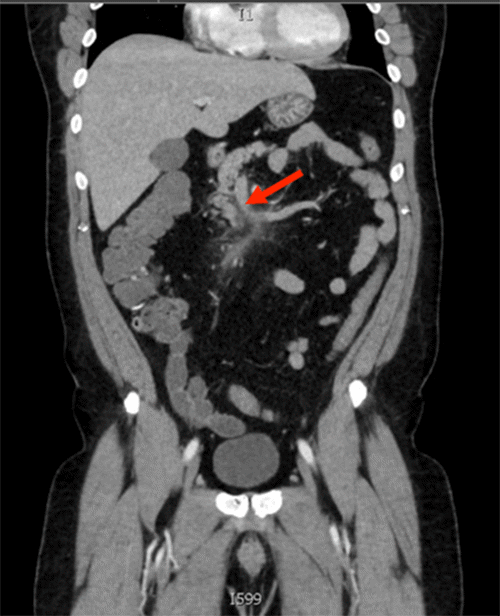

A 53-year-old Black male with a medical history of hyperaldosteronism, hypertension, and gastroesophageal reflux disease presented to the emergency department of a university-affiliated academic medical center with symptoms suggestive of appendicitis. A CT scan with contrast confirmed the diagnosis by demonstrating a dilated and inflamed appendix (Figure 1).

Figure 1. Contrast-enhanced CT Scan of Appendix. Published with Permission

The appendix appears dilated and inflamed (findings consistent with appendicitis)